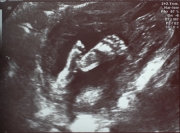

Рождественский аист с голубой колясочкой в клюве, дважды напутав с ее содержимым, в этот раз, кажется, обязался доставить в точности то, что предполагает цвет его драгоценной ноши. Двое опытных специалистов полтора часа гонялись за маленьким ...